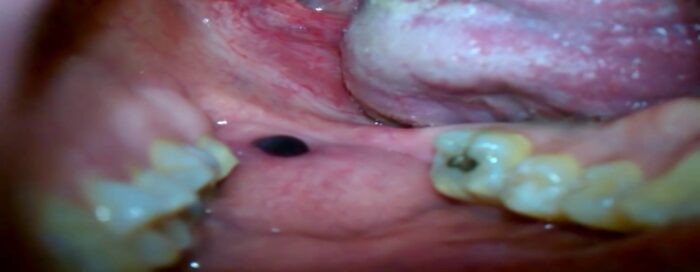

Causes Of A Black Spot Inside The Cheek

Looking in the mirror and seeing a black spot inside the cheek can be alarming, but is it something serious? The good news is that a dark spot inside your cheek is probably harmless. Consider these possible causes and see your dentist for a definitive diagnosis.

Amalgam Tattoos

If the spot inside your cheek is dark blue, gray or black, it could be a leakage from a dental filling. Amalgam tattoos aren't the permanent ink decorations on your skin that you can have done at a tattoo parlor. Amalgam is the silvery substance that your dentist uses to fill cavities, and it's made from a mixture of tin, zinc, mercury, copper and silver. Sometimes, after a dentist has filled a tooth, the filling mixture leaks, leaving behind a flat, painless dark spot that doesn't grow or change shape.

According to Brigham and Women's Hospital Division of Oral Medicine and Dentistry, amalgam tattoos are permanent, but they don't cause any harm. If the mark is inside your cheek, it's unlikely anyone will see it. However, if you think the spot looks unsightly, speak with your dentist about removal options.